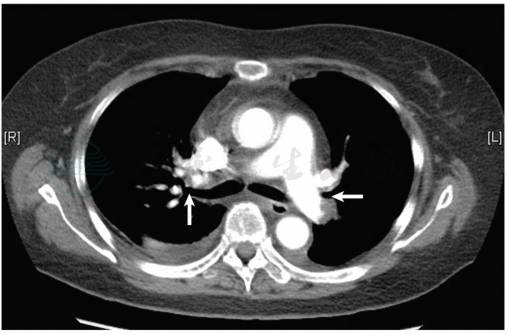

出院后2个月随访,胸闷、气短症状明显减轻,复查肺部CTA:双肺栓塞灶较前明显吸收(图2)。嘱长期利伐沙班抗凝,定期随访。

图2 肺动脉CTA示抗凝治疗2个月后双侧肺动脉血栓大部分溶解吸收(白箭)